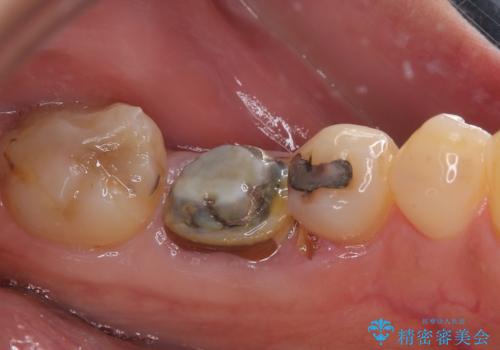

当院では、他院で抜歯と言われてきた歯を何とか保存する治療を多く行ってきましたが、レントゲン上で確認できるほど割れてしまっている歯はさすがに要抜歯と説明をし、インプラント治療を行うこととしました。

下顎大臼歯の抜歯即時埋入インプラント治療では、複数ある歯根のうち、後方の歯根部にインプラントを埋入することで一般的であり、今回破折して骨吸収が著しいのは前方の歯根であったため、事前に仮歯を用意した上で、抜歯即時埋入インプラントによる補綴治療を行うこととしました。